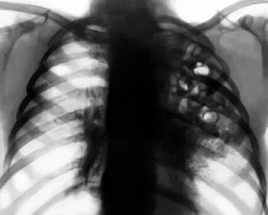

Диагностировать заболевание можно с помощью рентгенографии или компьютерной томографии грудной клетки (показывают инфильтраты (уплотнения) в легочной ткани), биотического анализа крови, общего анализа крови, анализа крови на газы, бактериологического посева мокроты.